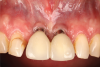

After 3 months of submerged healing, the operated area presented with limited keratinized mucosa on the buccal aspect (Figure 8). Therefore, a flap with two vertical incisions was designed starting from the palatal aspect of the two submerged implants. In addition, the mid-palatal portion of the flap was further extended toward the palatal aspect to obtain a roll flap that was de-epithelialized with a bur and eventually rolled to increase the interproximal soft tissue between the two implants (Figure 9). The flap was elevated in split-thickness fashion, with the soft tissue on top of the implants being removed to identify the cover screws (Figure 10). A substantial increase in soft-tissue thickness was observed at the buccal aspect of the implants compared to the first surgical procedure (Figure 11), when the implant fixtures were visible through a thin layer of connective tissue fibers adherent to the implant surfaces. The cover screws were removed, and temporary titanium abutments were connected.

Fig 8. Surgical site after 3 months.

Figure 8